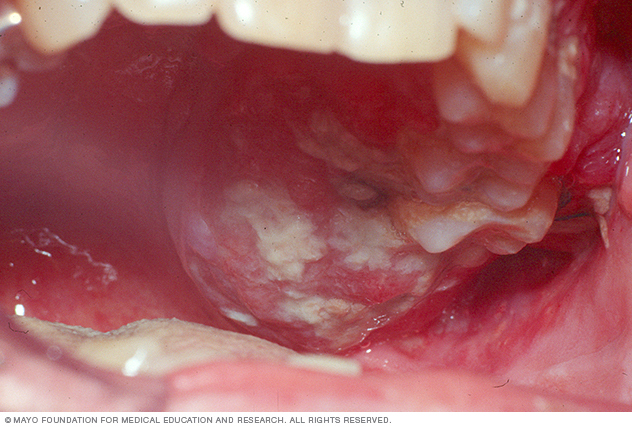

Xuất hiện mảng đổi màu trong miệng: Có thể là màu đỏ, trắng hay đen xuất hiện trong khoang miệng, bạn cần đi khám ngay. Thường những mảng đổi màu ở lưỡi, môi, nướu răng, hoặc thành đám dày trong miệng đều cần nghĩ tới bệnh ung thư.

U cục: Đối với nhiều trường hợp, người bệnh không bị đổi màu trong khoang miệng mà xuất hiện các loại u cục. Các loại khối u cục, người bệnh có thể dễ dàng phát hiện bằng mắt thường hoặc sờ tay. Với bất kỳ khối bất thường nào trên cơ thể kể cả trong khoang miệng hay ngoài môi bạn cần đến gặp bác sĩ để được thăm khám.